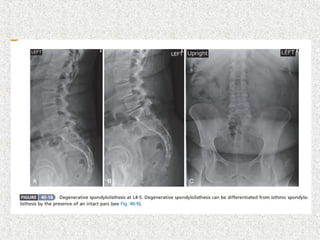

 LS spine X-ray

 AP

 Lat

 Lat flexion/extension

 Oblique if suspecting spondylolysis

Type VI,iatrogenic Most commontype L4-5 L5-S1 level common